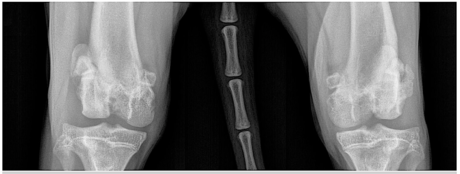

FIGURE 1. Radiographs of a 7-year-old male neutered domestic shorthaired cat that presented with chronic left hindlimb lameness. Medial patellar luxation (MPL) was diagnosed and treated conservatively until lameness worsened to grade 4/5. At the time of radiography, the patient was diagnosed with grade III MPL in the left hindlimb and grade II MPL in the right hindlimb. (A) Preoperative ventrodorsal view showing bowing of the tibia. Radiologist reported remodeling of the margin of the medial femoral trochlea on the left hindlimb. Note the medial location of the patella. (B) Preoperative mediolateral view. (C) Postoperative ventrodorsal view after a mini tightrope procedure, medial retinaculum release, and lateral fascia imbrication. CCL rupture was diagnosed during surgery. (D) Postoperative mediolateral view. Courtesy of VCA Animal Specialty Center of South Carolina, Columbia, South Carolina

Diagnosis of PL is primarily based on palpation of the affected stifle. Radiography can help determine the presence and degree of limb deformity and aid with planning of any surgical realignment procedures (FIGURES 1 and 2). Radiography can also determine the degree of osteoarthritis if present. On radiography, the patella will be visualized outside of the trochlear sulcus in grade III and IV PL and may be visualized within the trochlear sulcus in grade I and II luxations.4